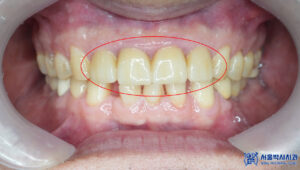

앞니는 심미적인 부위이기 때문에,

브릿지의 모양, 색상, 형태를

정밀하게 확인한 후에

영구접착을 진행했습니다.

환자분의 자연스러운 미소를 위해

세심한 조정을 거쳐

최적의 결과를 도출할 수 있도록

신경을 썼습니다.

마무리 후 사진입니다.